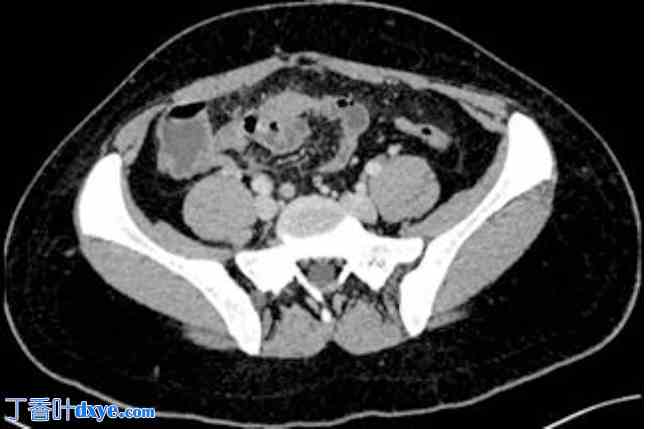

诊断评估:血液检查显示生物炎症综合征,伴有白细胞增多(15200个/立方毫米,C反应蛋白水平升高至65毫克/升)。脂血症和β-HCG水平正常。胸腹CT扫描显示腹腔内中等量游离积液,盆腔腹膜片增厚,但无气腹(图1)。CT扫描还显示少量炎性淋巴结。阑尾无肿大,卵巢呈多卵泡状(图2)。胸部CT扫描显示双侧基底实质实变,并伴有充气支气管征,与双侧基底肺炎相符。

图1.

腹腔内积液和盆腔腹膜片增厚